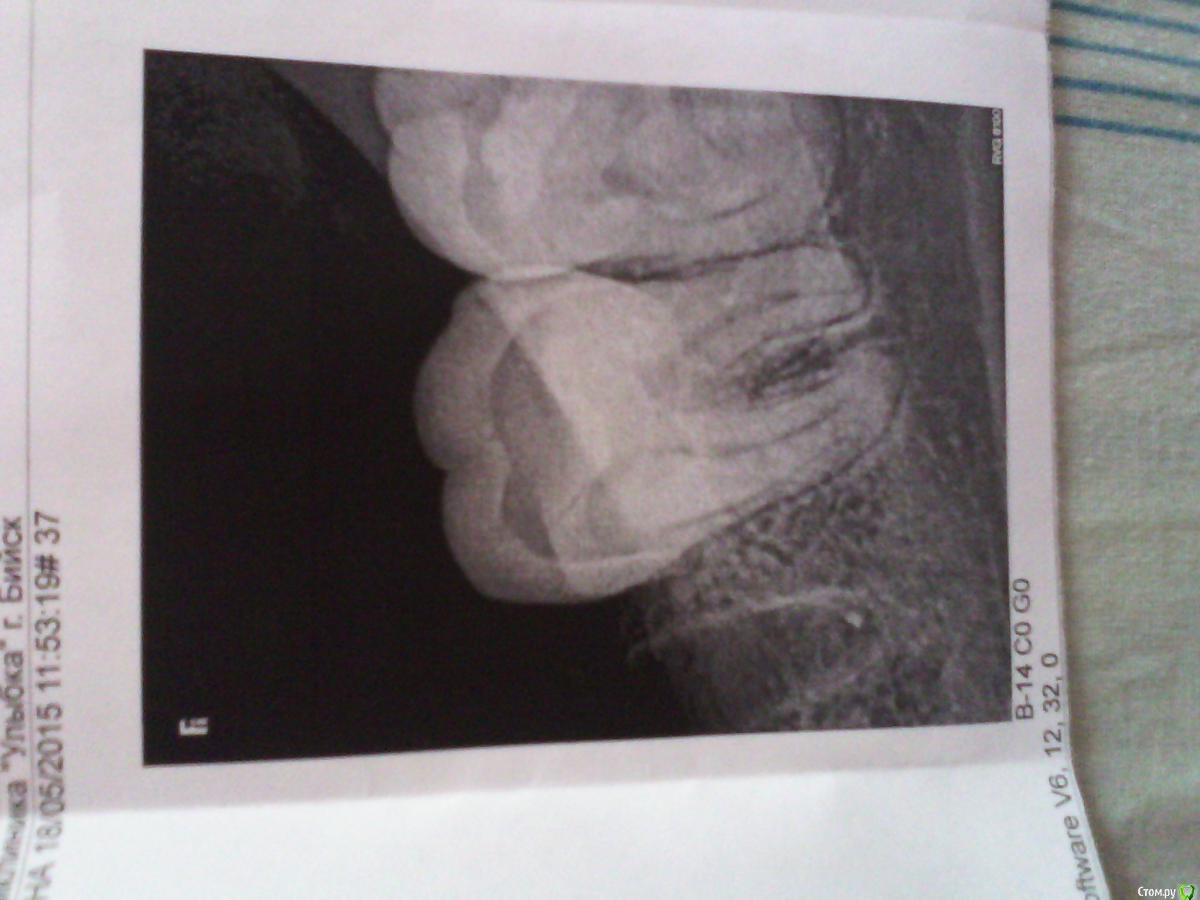

Ольга 2015 Опубликовано 18 мая, 2015 Поделиться Опубликовано 18 мая, 2015 (изменено) Здравствуйте, мне 34 года,месяц назад удалили нижнюю шестерку слева ,убирали по кусочкам, а четверг заметила, белый мешочек и гнойное отделяемое через свищевой ход на десне, возле уже (почти) заросшей лунки, на выходных обратилась к стоматологу ,сказали сделать рентген, сегодня сделала. Воспаление сняла-полоскание хлоргексидин, мазь-метрогил-дента, антибиотик доксициклин.Уважаемый доктор ,посмотрите снимок пожалуйста ,и опишите ситуацию, с уважением Ольга. Изменено 18 мая, 2015 пользователем Ольга 2015 Ссылка на комментарий

Bier Опубликовано 20 мая, 2015 Поделиться Опубликовано 20 мая, 2015 если есть свищ, надо туда залезть и почистить. 1 Ссылка на комментарий